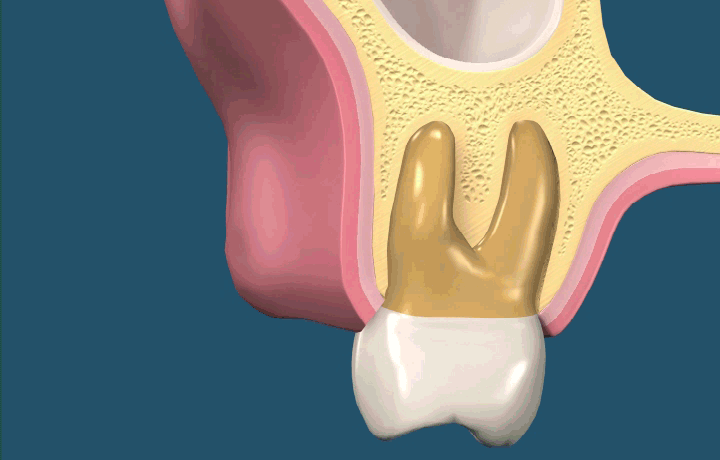

상악 구치부(어금니) 시술 시 상악동이라는 구조물 때문에 수술이 어려운 경우가 있습니다.

상악동은 위턱뼈 안쪽의 빈 공간을 말합니다. 상악동 거상술이란 상악동의 하방벽을 위로 들어올리고

그 공간에 뼈를 이식하여 임플란트 식립을 위한 뼈를 확보하는 수술로 시술자의 능숙한 시술과 고도의 기술이 필요한 수술입니다.